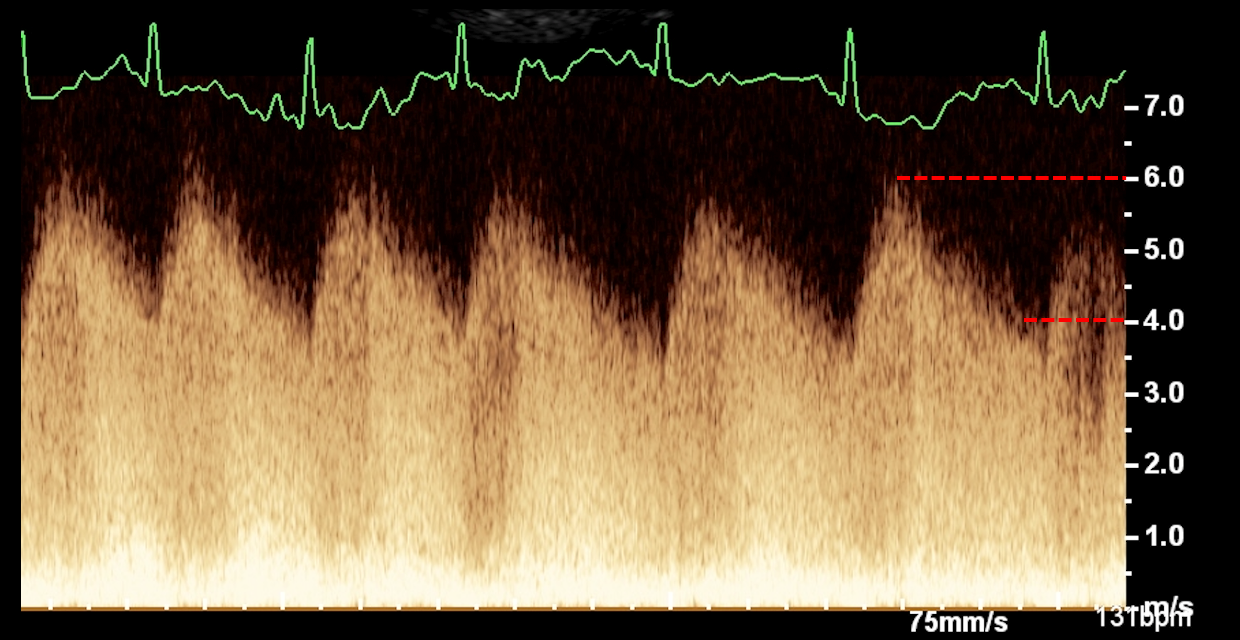

• Identifier, classifier et graduer les cardiopathies congénitales à partir des anomalies détectées en échocardiographie 2D, TM et Doppler.

• Interpréter de manière croisée les informations issues des différents modes échographiques (2D, TM, Doppler) pour affiner le diagnostic.

Analyse de cas cliniques illustrés par des images fixes et/ou des vidéos d’échocardiographie (2D, TM, Doppler).

Objectif : apprendre à repérer, décrire et interpréter les anomalies échographiques dans une démarche diagnostique rigoureuse, jusqu’à l’établissement de diagnostics différentiels.

Revue des bases en échocardiographie 2D, TM et Doppler appliquées aux cardiopathies congénitales.